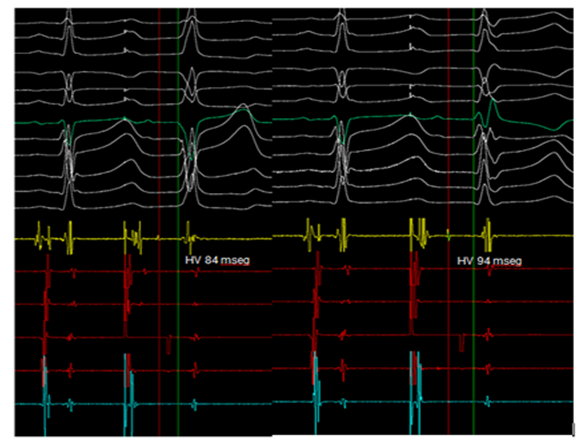

Certainly, the patient presented a regular, wide QRS complex tachycardia, with right bundle branch block morphology in precordial leads, inferior axis and positive precordial concordance (Figure 1). During the electrophysiological study, a decapolar catheter was placed in the coronary sinus, a quadripolar catheter in His, and another in a right ventricle tip. The baseline conduction times were within normal limits. During oversensing extra stimulation and with programmed atrial stimulation with decreasing cycles, progressive widening of the QRS complex was observed with left bundle branch block morphology but with a negative QRS complex in aVL and prolongation of the HV interval up to 84 msec. With even shorter cycles, the QRS complex morphology changed to right bundle branch block with greater prolongation of the HV interval up to 94 msec (Figure 2). With programmed atrial stimulation in the proximal coronary sinus, we observed a dual AV nodal pathway physiology with a single narrow echo beats. With shorter cycles and longer AV prolongation, clinical tachycardia was induced (Figure 3). This tachycardia presented an atrio-ventricular ratio of 1 to 1 with concentric retroconduction and variable VA intervals (mostly short).

Figure 2 (A) Oversensing extra stimulation with programmed atrial stimulation, with left bundle branch block aberrant complex and prolongation of the HV interval. (B) Right bundle branch block aberrant complex and greater prolongation of the HV interval seen in shorter cycles.